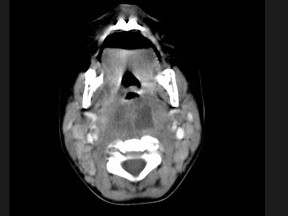

18.10個(gè)月大的嬰兒,發(fā)熱,曾患中耳炎,CT掃描如圖所示,請(qǐng)選擇正確的描述或診斷  (    )

正確答案:ABCD